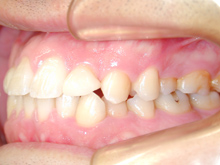

患者様は上顎前歯の脇の歯(側切歯)の隙間を閉じるご希望で来院されました。

矯正治療をご希望されましたが、空隙を閉鎖しても矮小歯の形を変えることができず、治療期間、費用を考えてポーセレンラミネートベニアで治療する事となりました。

写真撮影を行い、麻酔をせずにエナメル質の範囲で薄く歯質を削りきれいに、形成します。

本症例では曲面を少々切削しております。

研究用模型をつくり、患者様と患者様のご要望などの話をしながら修復物の形などを検討します。